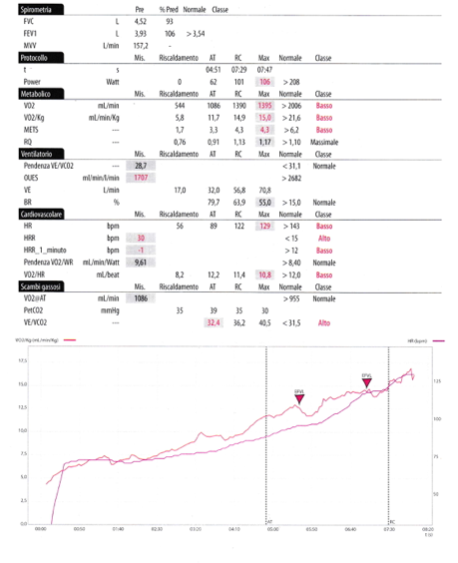

Al momento stiamo seguendo e “somministrando” la terapia con esercizio fisico a mesi di distanza dall’episodio di polmonite interstiziale da Sars Cov 2, dopo accurata valutazione tramite il test cardiopolmonare (e quindi applicando l’intensita’ piu’ corretta possibile, conoscendo il VO2 max , la soglia anaerobica ventilatoria e molti altri parametri che servono ad individualizzare il trattamento) che rappresenta il “gold standard” dei tests per studiare le tolleranza allo sforzo, che già, in al.cuni pazienti, ci ha permesso di vedere una severa diminuzione del consumo di ossigeno massimale , segno questo di una importante compromissione cardiorespiratoria e periferica tipica di questi pazienti.